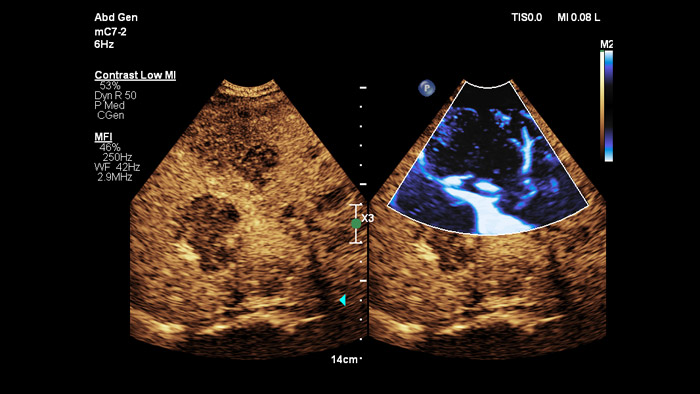

People come in many different shapes and sizes, with PureWave crystal technology you can improve penetration in difficult to scan body types, all while maintaining excellent detail resolution, Doppler sensitivity and contrast enhanced ultrasound (CEUS) performance.

PureWave crystal technology is the biggest breakthrough in piezoelectric transducer material in 40 years and is 85% more efficient than conventional piezoelectric materials, resulting in exceptional performance for all patient body types.